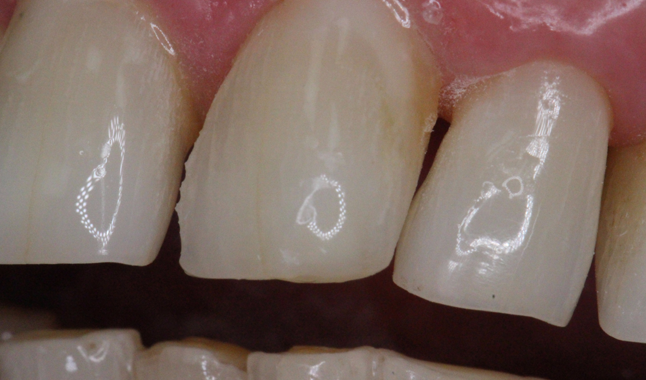

Anterior tooth in need of restoration.

Anterior tooth in need of restoration

Progressing to the anterior restoration, we completed our preparation and proceeded through our bonding steps again with the same universal adhesive. Because of the location of the restoration, we chose to use an esthetic composite system [Empress Direct; Ivoclar Vivadent].

Adhesion to both enamel and dentin achieved with universal adhesive [Futurabond U; VOCO].

Adhesion to both enamel and dentin achieved with universal adhesive [Futurabond U; VOCO]